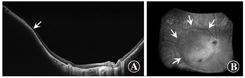

组织学切片和MRI检查显示,LRP2基因敲除小鼠模型分别在第15天和第21天出现眼轴增长和后巩膜葡萄肿(图4A,B)。脉络膜和RPE在葡萄肿边缘分离,这2层逐渐变薄,在进入视盘前消失。这些图像上不能清楚地识别Bruch膜。此外,视网膜明显变薄,在整个检测区域可见固缩的细胞体。这一发现表明,在这个模型中,有明显与视盘旁葡萄肿范围相对应的视盘旁萎缩区。这种构型与病理性近视患者的视盘周围γ区的后隆起相一致(图4C)[97]。

除了后巩膜葡萄肿,突变小鼠还发生视网膜和巩膜变薄以及脉络膜视网膜萎缩,类似于病理性近视患者。此外,LRP2基因敲除小鼠在一生中保持了恒定的眼压,这也与病理性近视患者的研究结果一致。因此,LRP2基因敲除小鼠可作为研究病理性近视病因学的动物模型。

最近已经开发出一种新的广域扫频OCT系统的原型机,使用多条扫描线生成扫描图,允许对23 mm×20 mm大小感兴趣区域和5 mm深处进行后巩膜葡萄肿的三维重建。Shinohara等[104]发现,广域OCT可以提供迄今为止最大分辨率和范围的后巩膜葡萄肿的断层图像,并可能取代3D-MRI评估后巩膜葡萄肿。广域OCT显示葡萄肿边缘一致性的变化,表现为从视网膜周边到葡萄肿边缘脉络膜逐渐变薄,再从葡萄肿边缘向后极部逐渐增厚,并伴有葡萄肿边缘巩膜曲率半径的改变(图8)。

超广域OCT被认为是鉴别儿童病理性近视的有效方法。其优势之一是可以看到神经视网膜的结构,并且可以检测葡萄肿和视网膜脉络膜并发症之间的关系。Shinohara等[106]发现,在葡萄肿眼中,近视黄斑区视网膜劈裂仅在葡萄肿区域内观察到。没有葡萄肿的眼近视黄斑区视网膜劈裂呈弥漫性。Takahashi等[107]分析了玻璃体粘连与葡萄肿的关系。